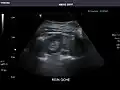

Renal ultrasonography

Ultrasound scan of a kidney (right side)

Ultrasonography of the kidneys is essential in the diagnosis and management of kidney-related diseases. The kidneys are easily examined, and most pathological changes in the kidneys are distinguishable with ultrasound.[7]